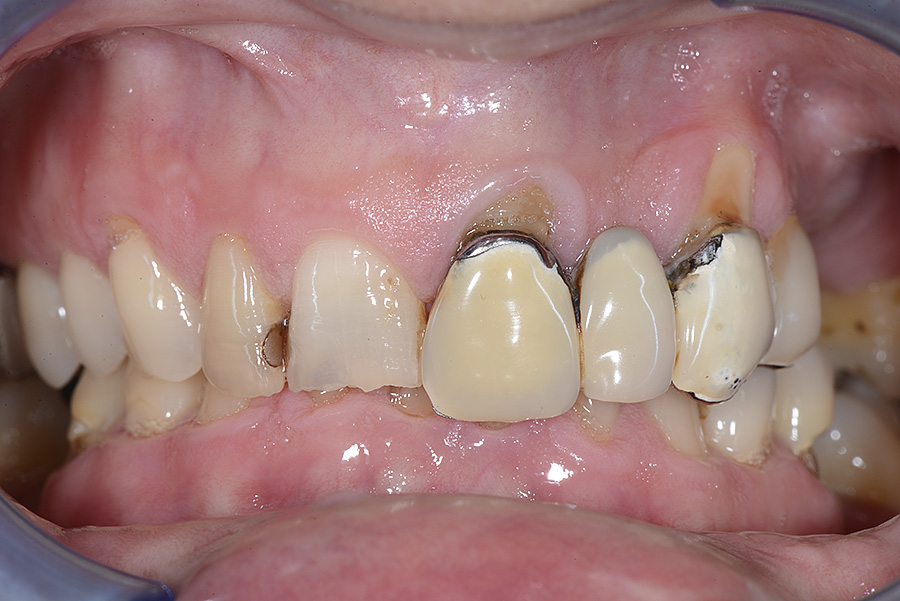

PREMESSA: in seguito all’estrazione dell’incisivo laterale superiore di destra, resasi necessaria per cause batteriche, si decide di affrontare il caso con il posizionamento di un impianto in sostituzione dell’elemento mancante dopo guarigione del sito infetto. Con tecniche rigenerative sia dei tessuti ossei mancanti a causa dell’infezione pregressa, sia dei tessuti gengivali che appaiono inizialmente troppo spostati in alto, si ripristina una corretta morfologia delle parabole (contorni) gengivali e delle papille interdentali (triangoli di gengiva tra due denti vicini).